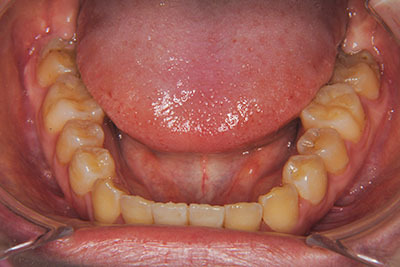

おとなの方でも矯正治療をあきらめないでください!

子供の頃に矯正治療を行う方が治療期間が短く済むというのは、確かですが、矯正治療は患者様の意識も重要です。

いくら歯が動き易くとも、本人がやる気でなければ効果は出ませんし、むし歯発生のリスクも高まります。おとなの方は顎の成長が終わっているため、治療の計画が立てやすいとも言えます。「もう大人だから…」とあきらめず、一度ご相談ください。